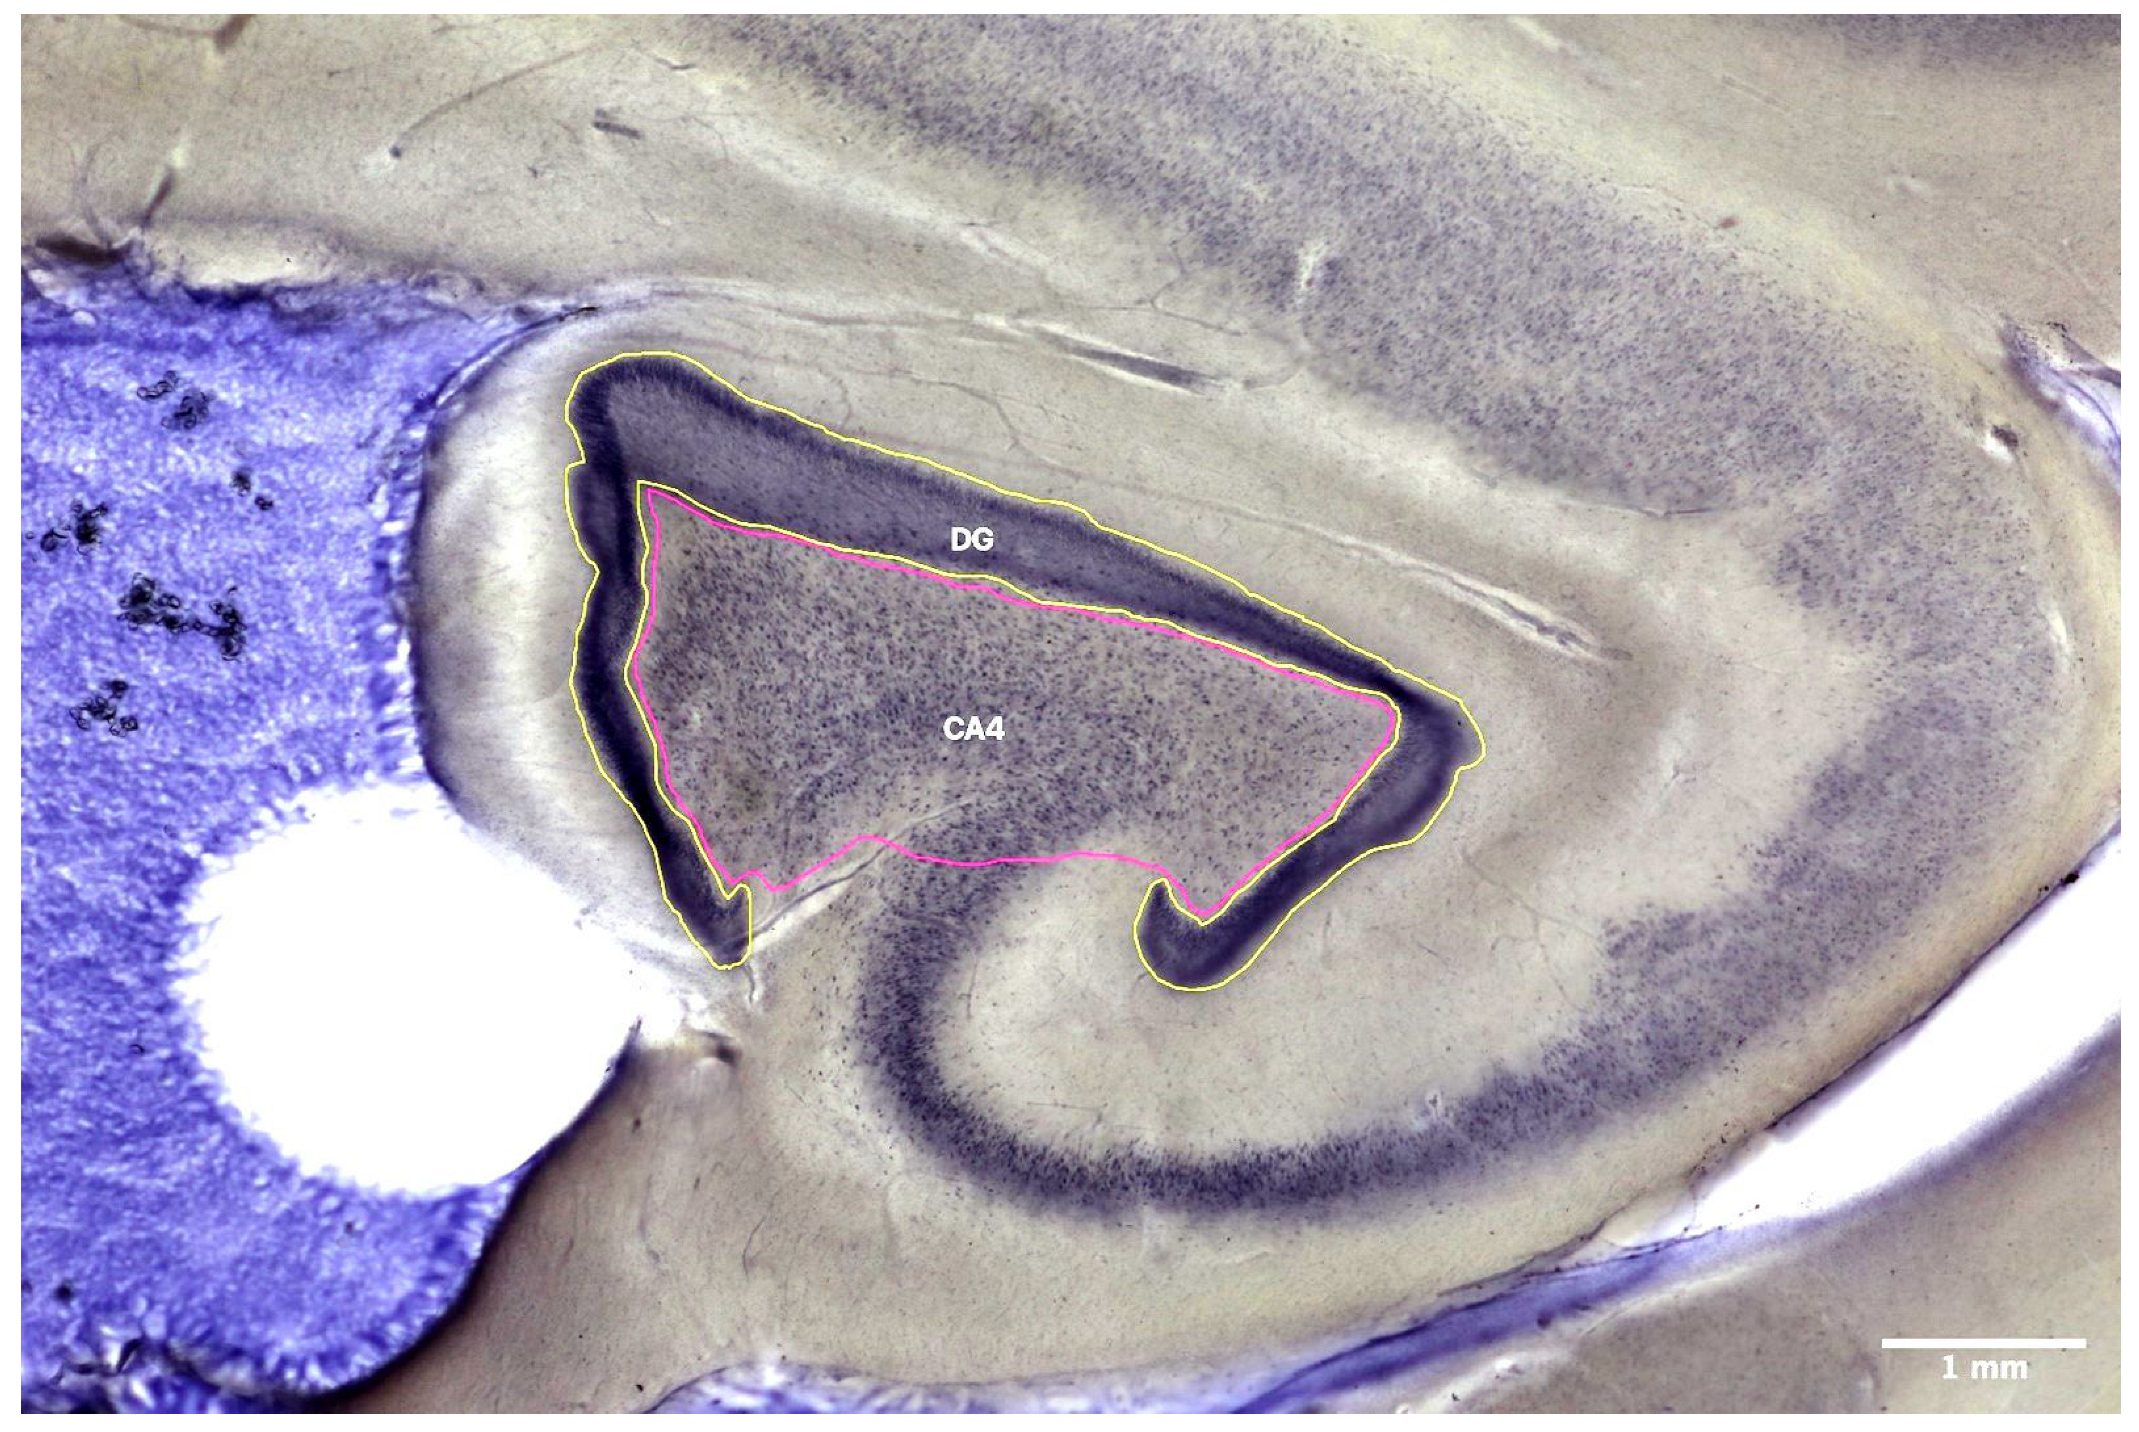

2.3. Stereological Analyses